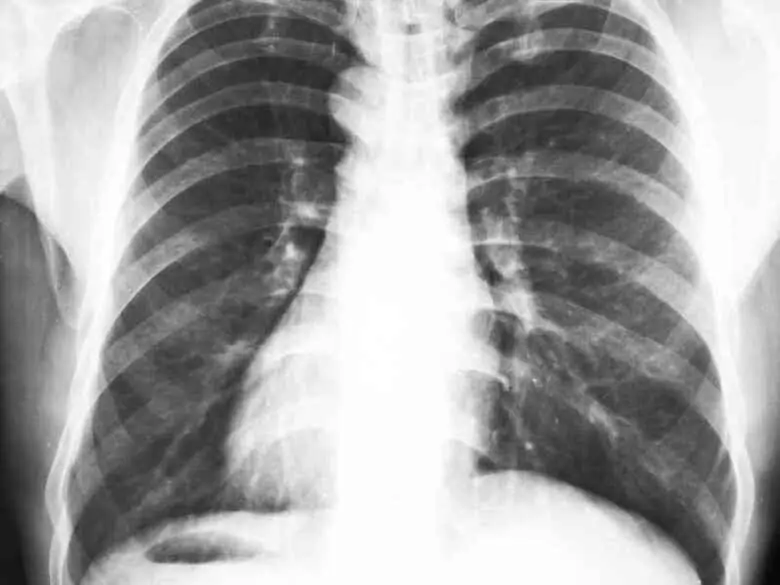

Ir a: Síntomas y curso de la enfermedad Cuándo acudir al médico Tratamiento Publicidad: Síntomas y curso de la enfermedad pecho de pollo Cuándo acudir al médico y tratamiento pecho de pollo Tratamiento pecho de pollo